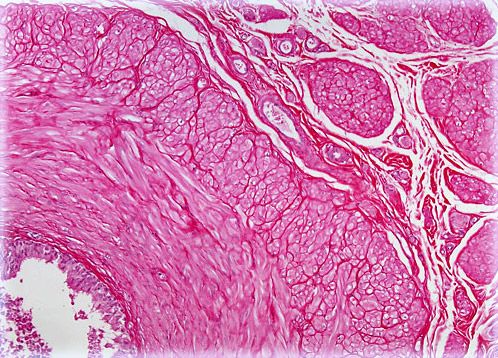

Ductus Deferens

The ductus deferens, also known as the vas deferens, is a paired duct, or tube, that is part of the male reproductive system in mammals. Each ductus deferens extends from the epididymis to the pelvic region.